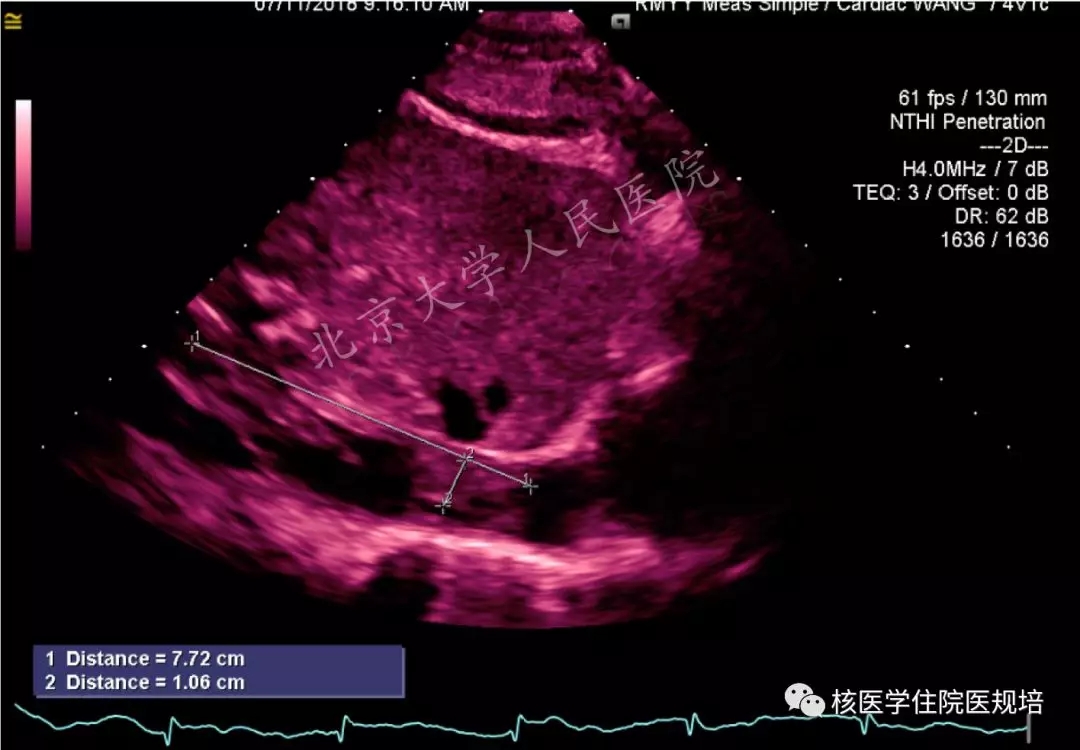

超声心动提示:右房、右室、下腔静脉占位(图1-2),三尖瓣功能性狭窄及轻度反流。

1.右房内低回声团块影,附着于三尖瓣右房面,随心动周期介于右心房及右心室之间摆动。

2.下腔静脉内可见附着于管壁不规则回声影